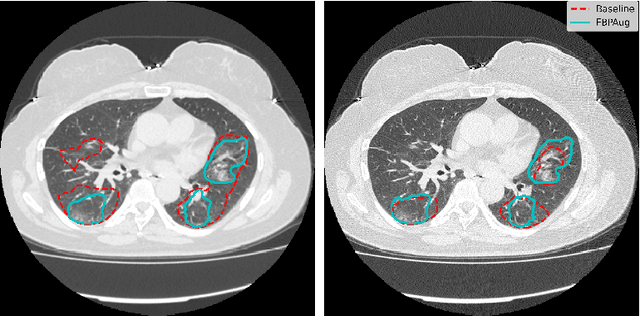

Abstract:Domain shift is one of the most salient challenges in medical computer vision. Due to immense variability in scanners' parameters and imaging protocols, even images obtained from the same person and the same scanner could differ significantly. We address variability in computed tomography (CT) images caused by different convolution kernels used in the reconstruction process, the critical domain shift factor in CT. The choice of a convolution kernel affects pixels' granularity, image smoothness, and noise level. We analyze a dataset of paired CT images, where smooth and sharp images were reconstructed from the same sinograms with different kernels, thus providing identical anatomy but different style. Though identical predictions are desired, we show that the consistency, measured as the average Dice between predictions on pairs, is just 0.54. We propose Filtered Back-Projection Augmentation (FBPAug), a simple and surprisingly efficient approach to augment CT images in sinogram space emulating reconstruction with different kernels. We apply the proposed method in a zero-shot domain adaptation setup and show that the consistency boosts from 0.54 to 0.92 outperforming other augmentation approaches. Neither specific preparation of source domain data nor target domain data is required, so our publicly released FBPAug can be used as a plug-and-play module for zero-shot domain adaptation in any CT-based task.